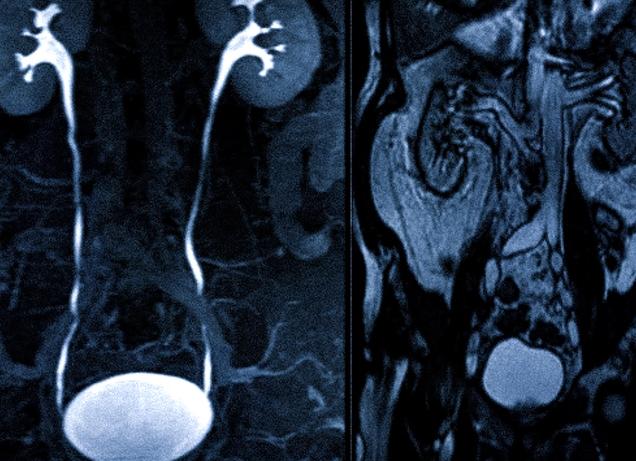

МРТ мочевого пузыря в большинстве случаев является частью комплексной томографии органов малого таза или выделительной системы (МРТ почек).

При необходимости для повышения точности исследования в кровь пациента перед процедурой вводят контрастное вещество. Распространяясь по кровотоку, оно локализуется в патологическом новообразовании, позволяя оценить его размеры и местоположение.

Стрелкой показана опухоль в просвете мочевого пузыря на МР-томограмме